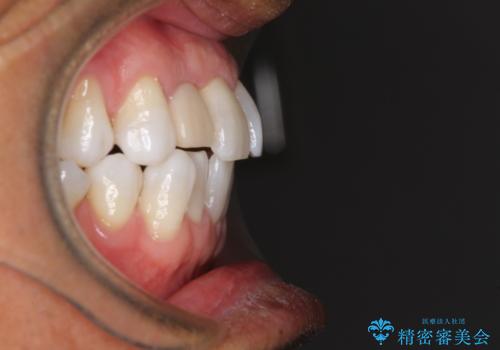

治療途中の前歯を治したい インビザライン矯正とオールセラミッククラウン

- 治療途中の前歯と上下前歯のデコボコ気にして来院された患者様です。

前歯のデコボコはインビザラインにより歯列を整え、その後に、前歯などをオーダーメイドタイプのオールセラミッククラウンにて補綴治療することとしました。

長時間のマウスピース装着に協力いただき、短期間で歯列をしっかりと改善することができました。

ホームホワイトニングを併用していただいたので、とても明るい口元に仕上がり、患者様には大変満足していただきました。